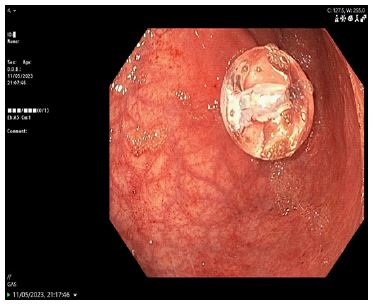

A temporary Foley catheter secured the tract. Subsequent endoscopy did not visualize the tube in the duodenum but found the gastrostomy device within the stomach (Figure 1). A new 14F replacement tube was inserted. The duodenal component seen on CT was presumed likely to pass spontaneously (Figure 2), and the patient was monitored for obstruction.